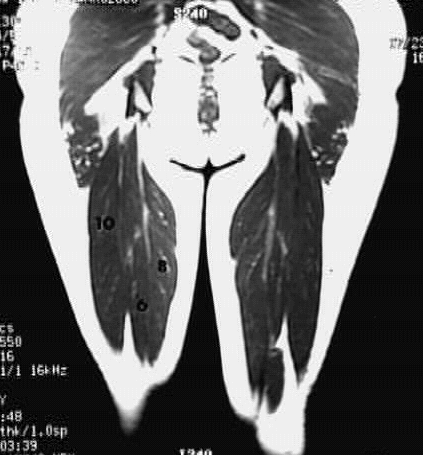

Lower Limbs: Thigh Coronal Zoom 3 of 3